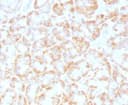

IgG1Applications:

IHC-PFormat: